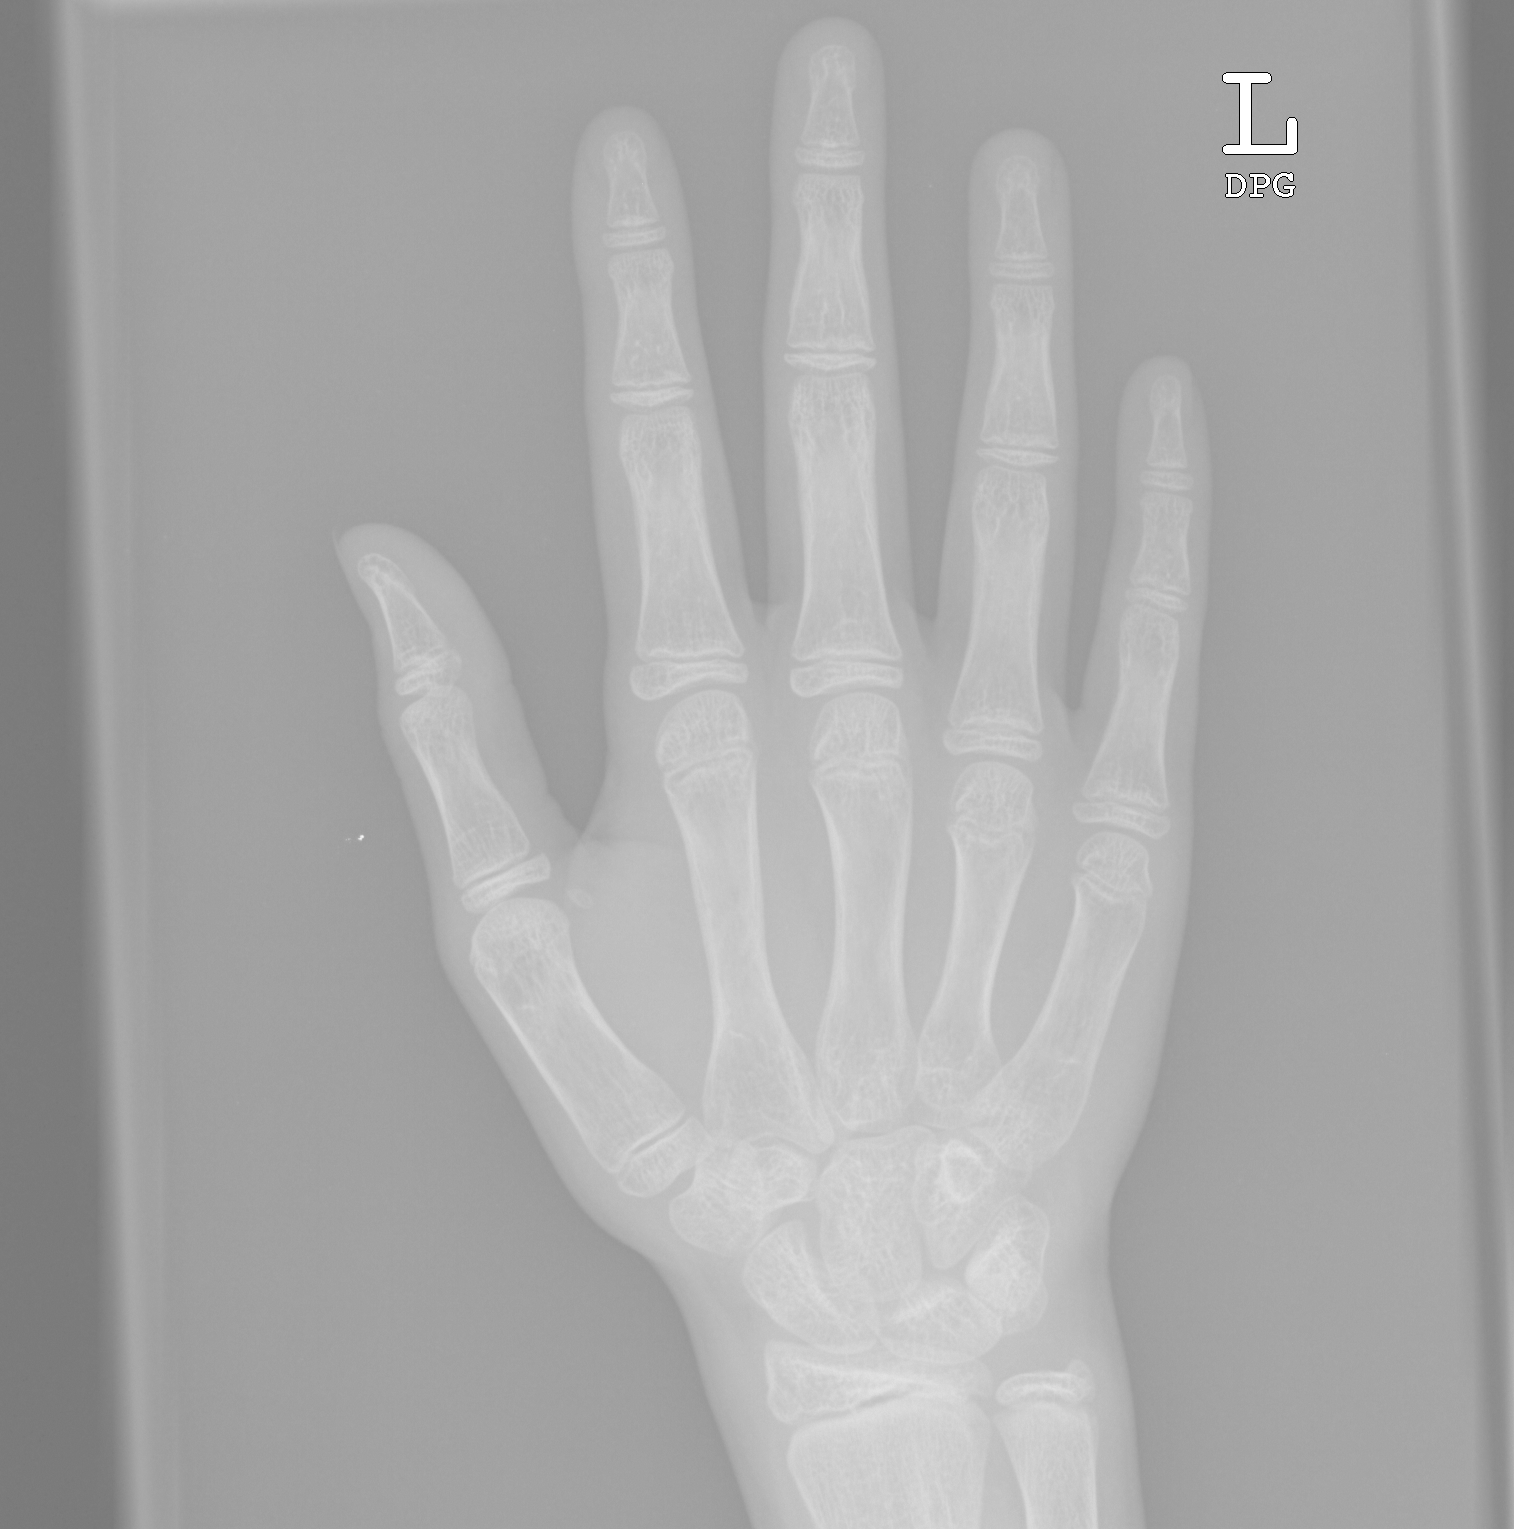

Propose a novel weakly-supervised learning approach for Bone Age Assessment, which can discover and extract the discriminative bone parts without human prior. State-of-art performance has been achieved, and the proposed method exhibits interpretability, consistency and inspiration with human prior knowledge.